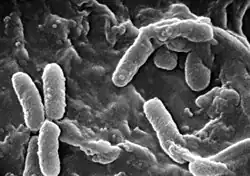

La enfermedad pulmonar resulta del bloqueo de las vías aéreas más pequeñas con el moco espeso característico de la fibrosis quística. La inflamación y la infección producen daño a los pulmones y cambios estructurales que conducen a una variedad de síntomas. En las etapas iniciales, comúnmente se presentan tos incesante, producción copiosa de flema, y una disminución en la capacidad aeróbica. Muchos de estos síntomas ocurren cuando ciertas bacterias (fundamentalmente, Pseudomonas aeruginosa) que normalmente viven en el moco espeso, crecen en forma descontrolada y causan neumonía. En estados avanzados de la FQ, los cambios en la arquitectura del pulmón producen dificultades respiratorias crónicas.

Los pulmones de las personas con Fibrosis Quística son colonizados e infectados por bacterias desde edades tempranas. Los microorganismos que se propagan en estos pacientes, prosperan en el moco anómalo acumulado en las vías respiratorias más estrechas. El moco glutinoso estimula el desarrollo de microambientes bacterianos (biofilms) que resultan difíciles de penetrar para las células inmunes y los antibióticos. Por su parte, los pulmones responden al daño continuo, infligido por las secreciones espesas y las infecciones crónicas, remodelando gradualmente las vías respiratorias inferiores (bronquiectasia), lo que vuelve a la infección aún más difícil de erradicar.[22]

Con el paso del tiempo, cambian tanto el tipo de bacterias que afectan a estos pacientes, como las características específicas con que las mismas se presentan. En una primera etapa, ciertas bacterias ordinarias como Staphylococcus aureus y Haemophilus influenzae colonizan e infectan los pulmones. Más tarde, sin embargo, prevalecen Pseudomonas aeruginosa (y, a veces, el complejo Burkholderia cepacia, integrado por diferentes especies de Burkholderia). Una vez diseminadas por las vías respiratorias, estas bacterias se adaptan al medio y desarrollan resistencia a los antibióticos convencionales. Pseudomonas puede adquirir ciertas características especiales, dando lugar a la formación de grandes colonias —estas cepas son conocidas como Pseudomonas «mucoide», y son raras en personas libres de la enfermedad—.[22]